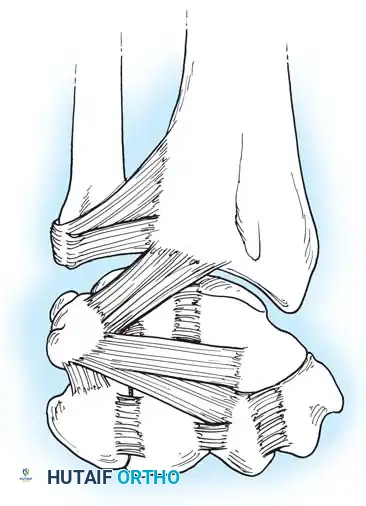

The Triangular Fibrocartilage Complex (TFCC)

The distal ulna articulates with the radius at the sigmoid notch, accommodating the ulnar head through approximately two-thirds of its rotational arc. The distal ulna is inclined at approximately 20 degrees relative to the radius.

Separating the hyaline cartilage-covered ulnar head from the carpus is the TFCC, a critical chondroligamentous stabilizer first comprehensively described by Palmer and Werner. The TFCC is the primary stabilizer of the DRUJ and the ulnar carpus.

* Dorsal and Volar Radioulnar Ligaments: The primary stabilizers of the DRUJ during pronation and supination.

Surgical Warning: When performing ulnar-sided surgical approaches or arthroscopy, extreme care must be taken to preserve the foveal attachments of the radioulnar ligaments. Disruption here leads to profound DRUJ instability that cannot be salvaged merely by repairing the articular disc.